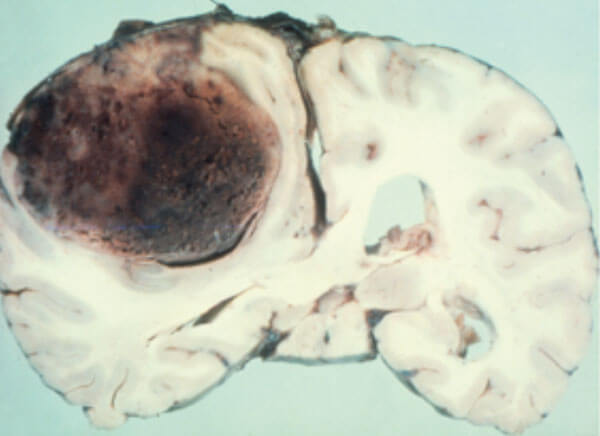

Figure 2: Pathology of large convexity meningioma compressing the brain with intrinsic haemorrhage.

Meningiomas arising from the tuberculum sellae cause early compression of the optic nerves or chiasma and can be mistaken clinically for a pituitary tumour or aneurysm. Meningiomas arising from the peripheral meninges grow slowly indent, compress the adjacent brain as seen in Figure 2, and if arising in the parietal or occipital areas may present with homonymous visual field defects. We also encounter patients with large frontal meningiomas originating from the falx, crista galli or olfactory groove (Figure 3) presenting to the eye clinic with headache and minimal general symptoms, but in most of such cases papilloedema will be present leading to the diagnosis.